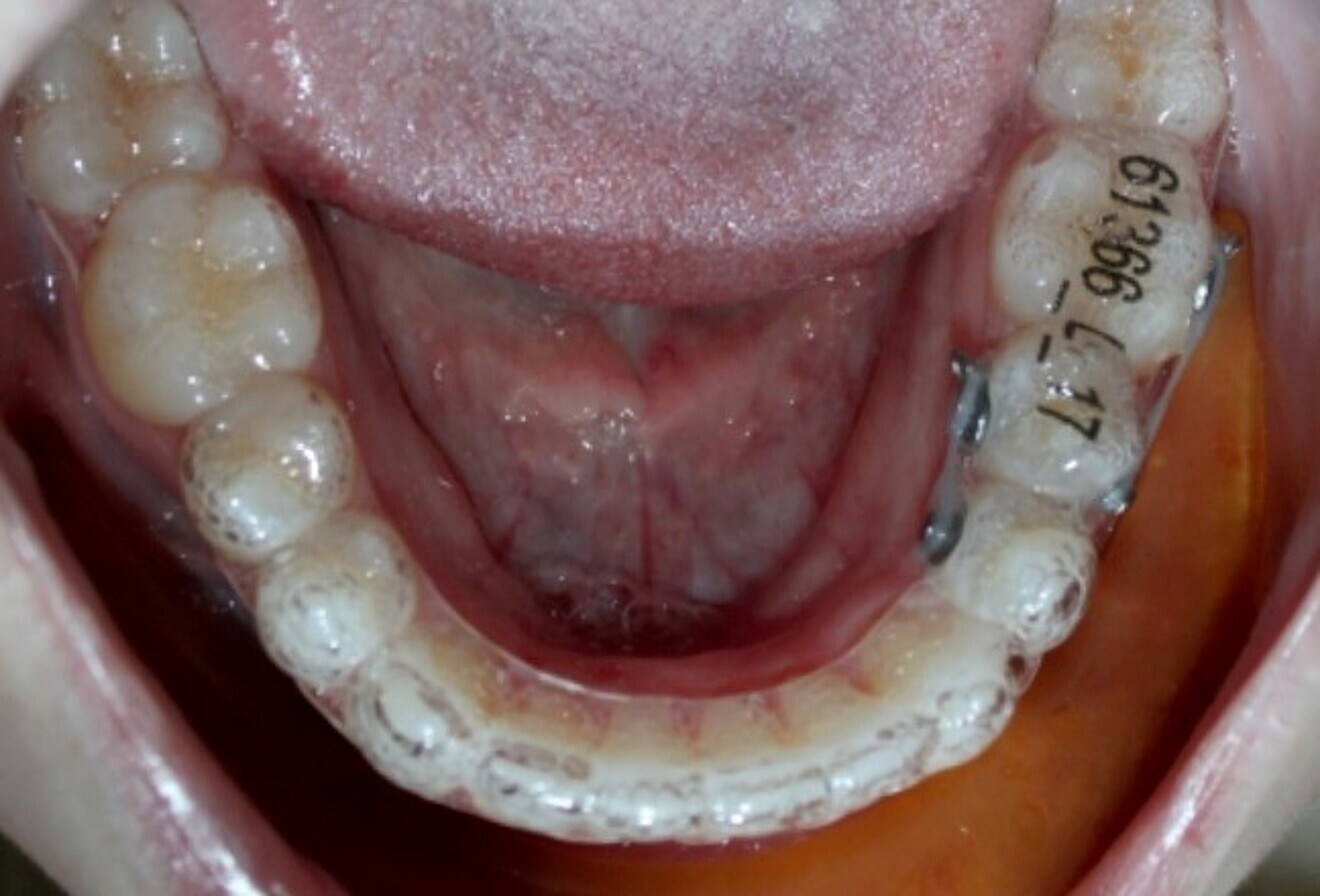

Aligners alone will fail because the plastic simply cannot adequately deliver the appropriate rotational couples—especially in cylindrical teeth. This is so despite ingenious attachment combinations that will indeed achieve some rotation, but not much. Instead use bonded buttons and elastomerics strategically placed into precision cut-outs of the first round of aligners and activated to produce force couples that will indeed rotate teeth (Figs. 1–3). The outcome is much more assured rotations in a shorter amount of time and with less chance of loss of aligner tracking.

Fig. 1: Severely rotated mandibular left second premolar.

Fig. 2: Underway with rotational couples.

Fig. 3: After four months of de-rotation.